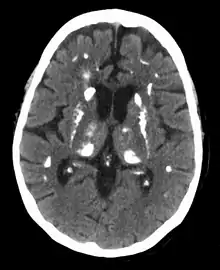

![]() الغدة الدرقية والغدة جارة الدرقية. الغدة الدرقية والغدة جارة الدرقية. | |